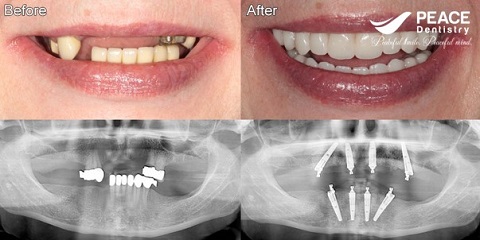

(Australian patient has used denture for 12 years and then decide to get all on 4 in Vietnam with 1/3 the price in Australia)

(All on 4 Implants for a Korean patient after 3 year using Crown & bridge)